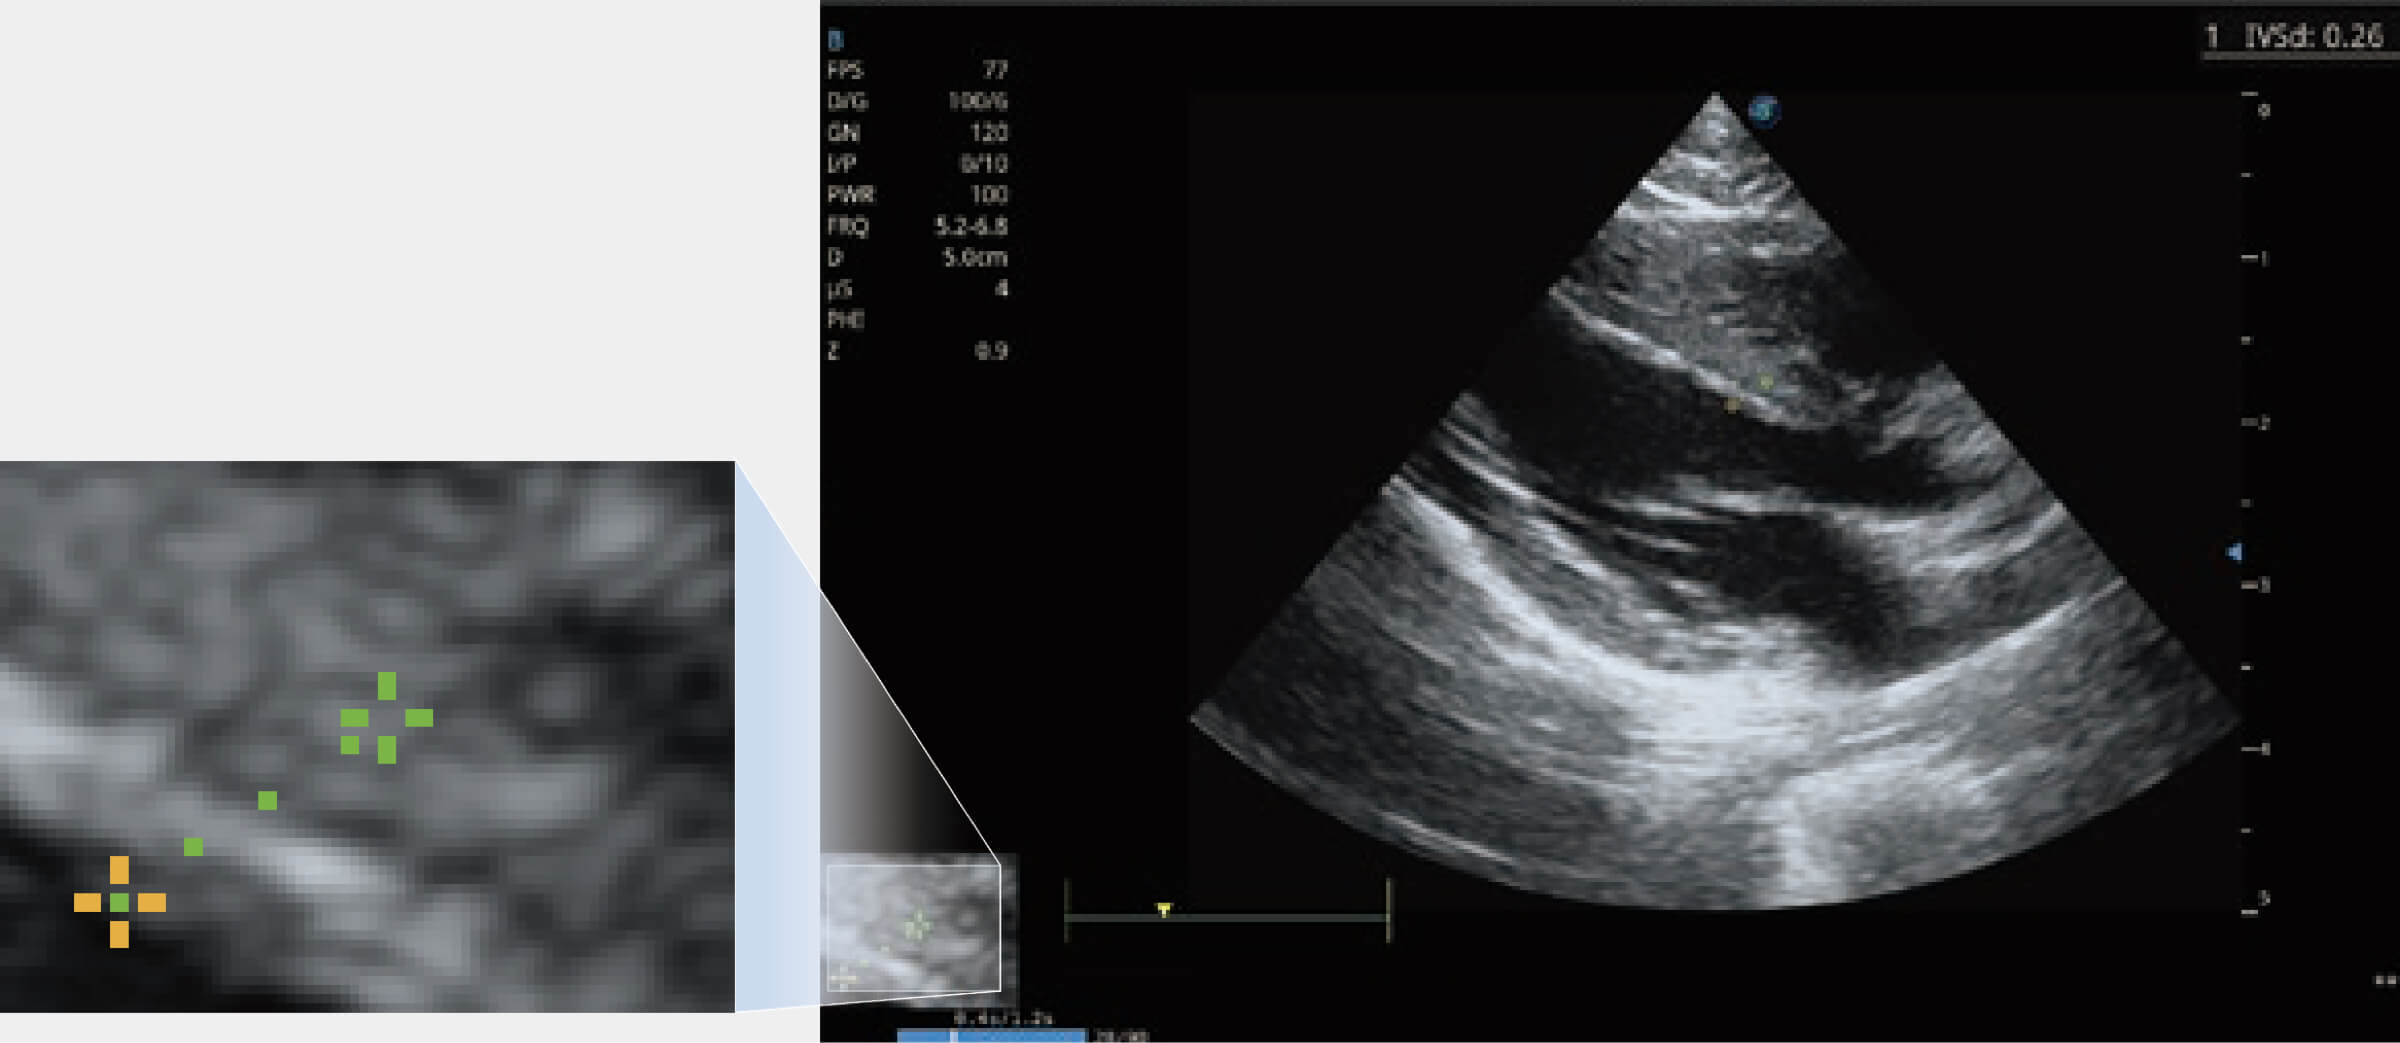

提供解剖示意圖、標(biāo)準(zhǔn)超聲圖像、掃查手法涂和操作者實(shí)時(shí)檢查圖像,指導(dǎo)操作者進(jìn)行標(biāo)準(zhǔn)切面的正確掃查。